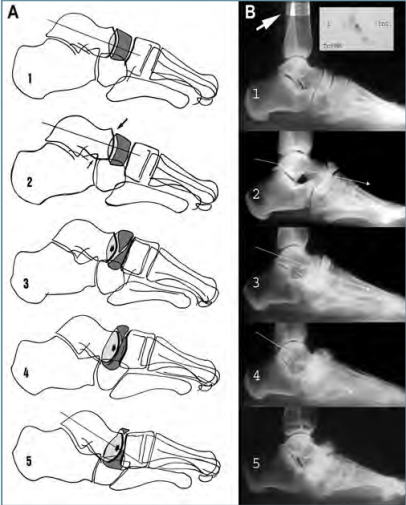

Les proves inclouen des de la realització d’exercicis físics fins a l’anàlisi del cervell mitjançant els elèctrodes connectats a moderns escàners.

Els científics t’observaran ai ompliran diverses escales mentre simules que jugues. També escanejaran el teu cervell, amb la finalitat de saber quines parts del mateix s’activen d’acord amb diferents estímuls.

Les tècniques d’obtenció d’imatges cerebrals s’apliquen tant a esportistes com a persones que no ho són, generalment, amb finalitats mèdiques.

Per exemple, la tomografia assistida per ordinador és un procediment que utilitza raigs X (radiació electromagnètica que produeix imatges de l’interior del cos) amb la finalitat de detectar anomalies en el cervell. Quan t’apliquen aquesta tècnica estaràs acostat immòbil sobre una mesa que passarà a través d’un gran escàner. Aquesta màquina crearà imatges bidimensionals o tridimensionals del teu cos.

La tomografia del crani s’utilitza principalment per a la detecció de tumors cerebrals, infeccions, accidents cerebrovasculars o lesions per traumatismes al cap i al rostre que pots provocar-te practicant futbol.

Aquest procediment com portar precaucions especials com que treballa amb radiació. Per expressar la dosi de radiació absorbida per la matèria viva s’usa la unitat de mesura anomenada sievert (Sv).